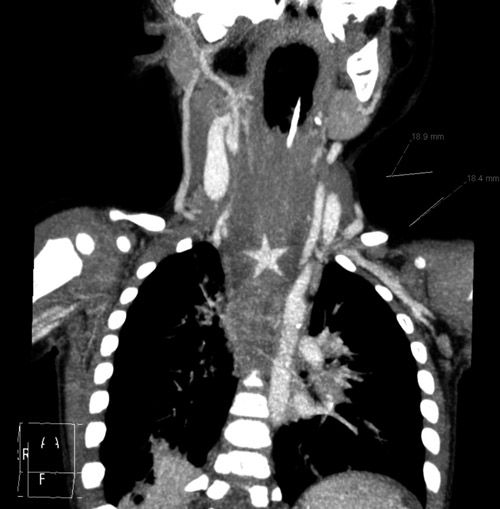

En sju måneder gammel gutt kom til barneavdelingen grunnet sikling og brekningstendens under et grøtmåltid. Røntgen oesophagus/thorax var normalt. Etter noen observasjonstid ble han bedre og kunne reise hjem. Fire måneder senere kom han til barnepoliklinikken grunnet vedvarende problemer med brekninger av all ikke-most mat. Ved øvre endoskopi fant man et ulcus i oesophagus. Etter avtale med barnekirurg ble det startet med protonpumpehemmer og avtalt kontroll etter fire uker. To uker senere ble pasienten innlagt akutt med tungpusthet. Røntgen thorax viste da breddeforøkt mediastinum og ultralydundersøkelse viste fortykket oeøsophagus med impresjon i trachea. På CT thorax ble det funnet bilaterale infiltrater og store lymfeknuter i hilum. Denne avslørte også et stjerneformet fremmedlegeme i oesophagusveggen forenlig med en 18 mm stor plastikkstjerne fra julepynt. Han ble overflyttet til barnekirurgisk avdeling hvor stjernen ble fjernet endoskopisk. Symptomene forsvant umiddelbart.